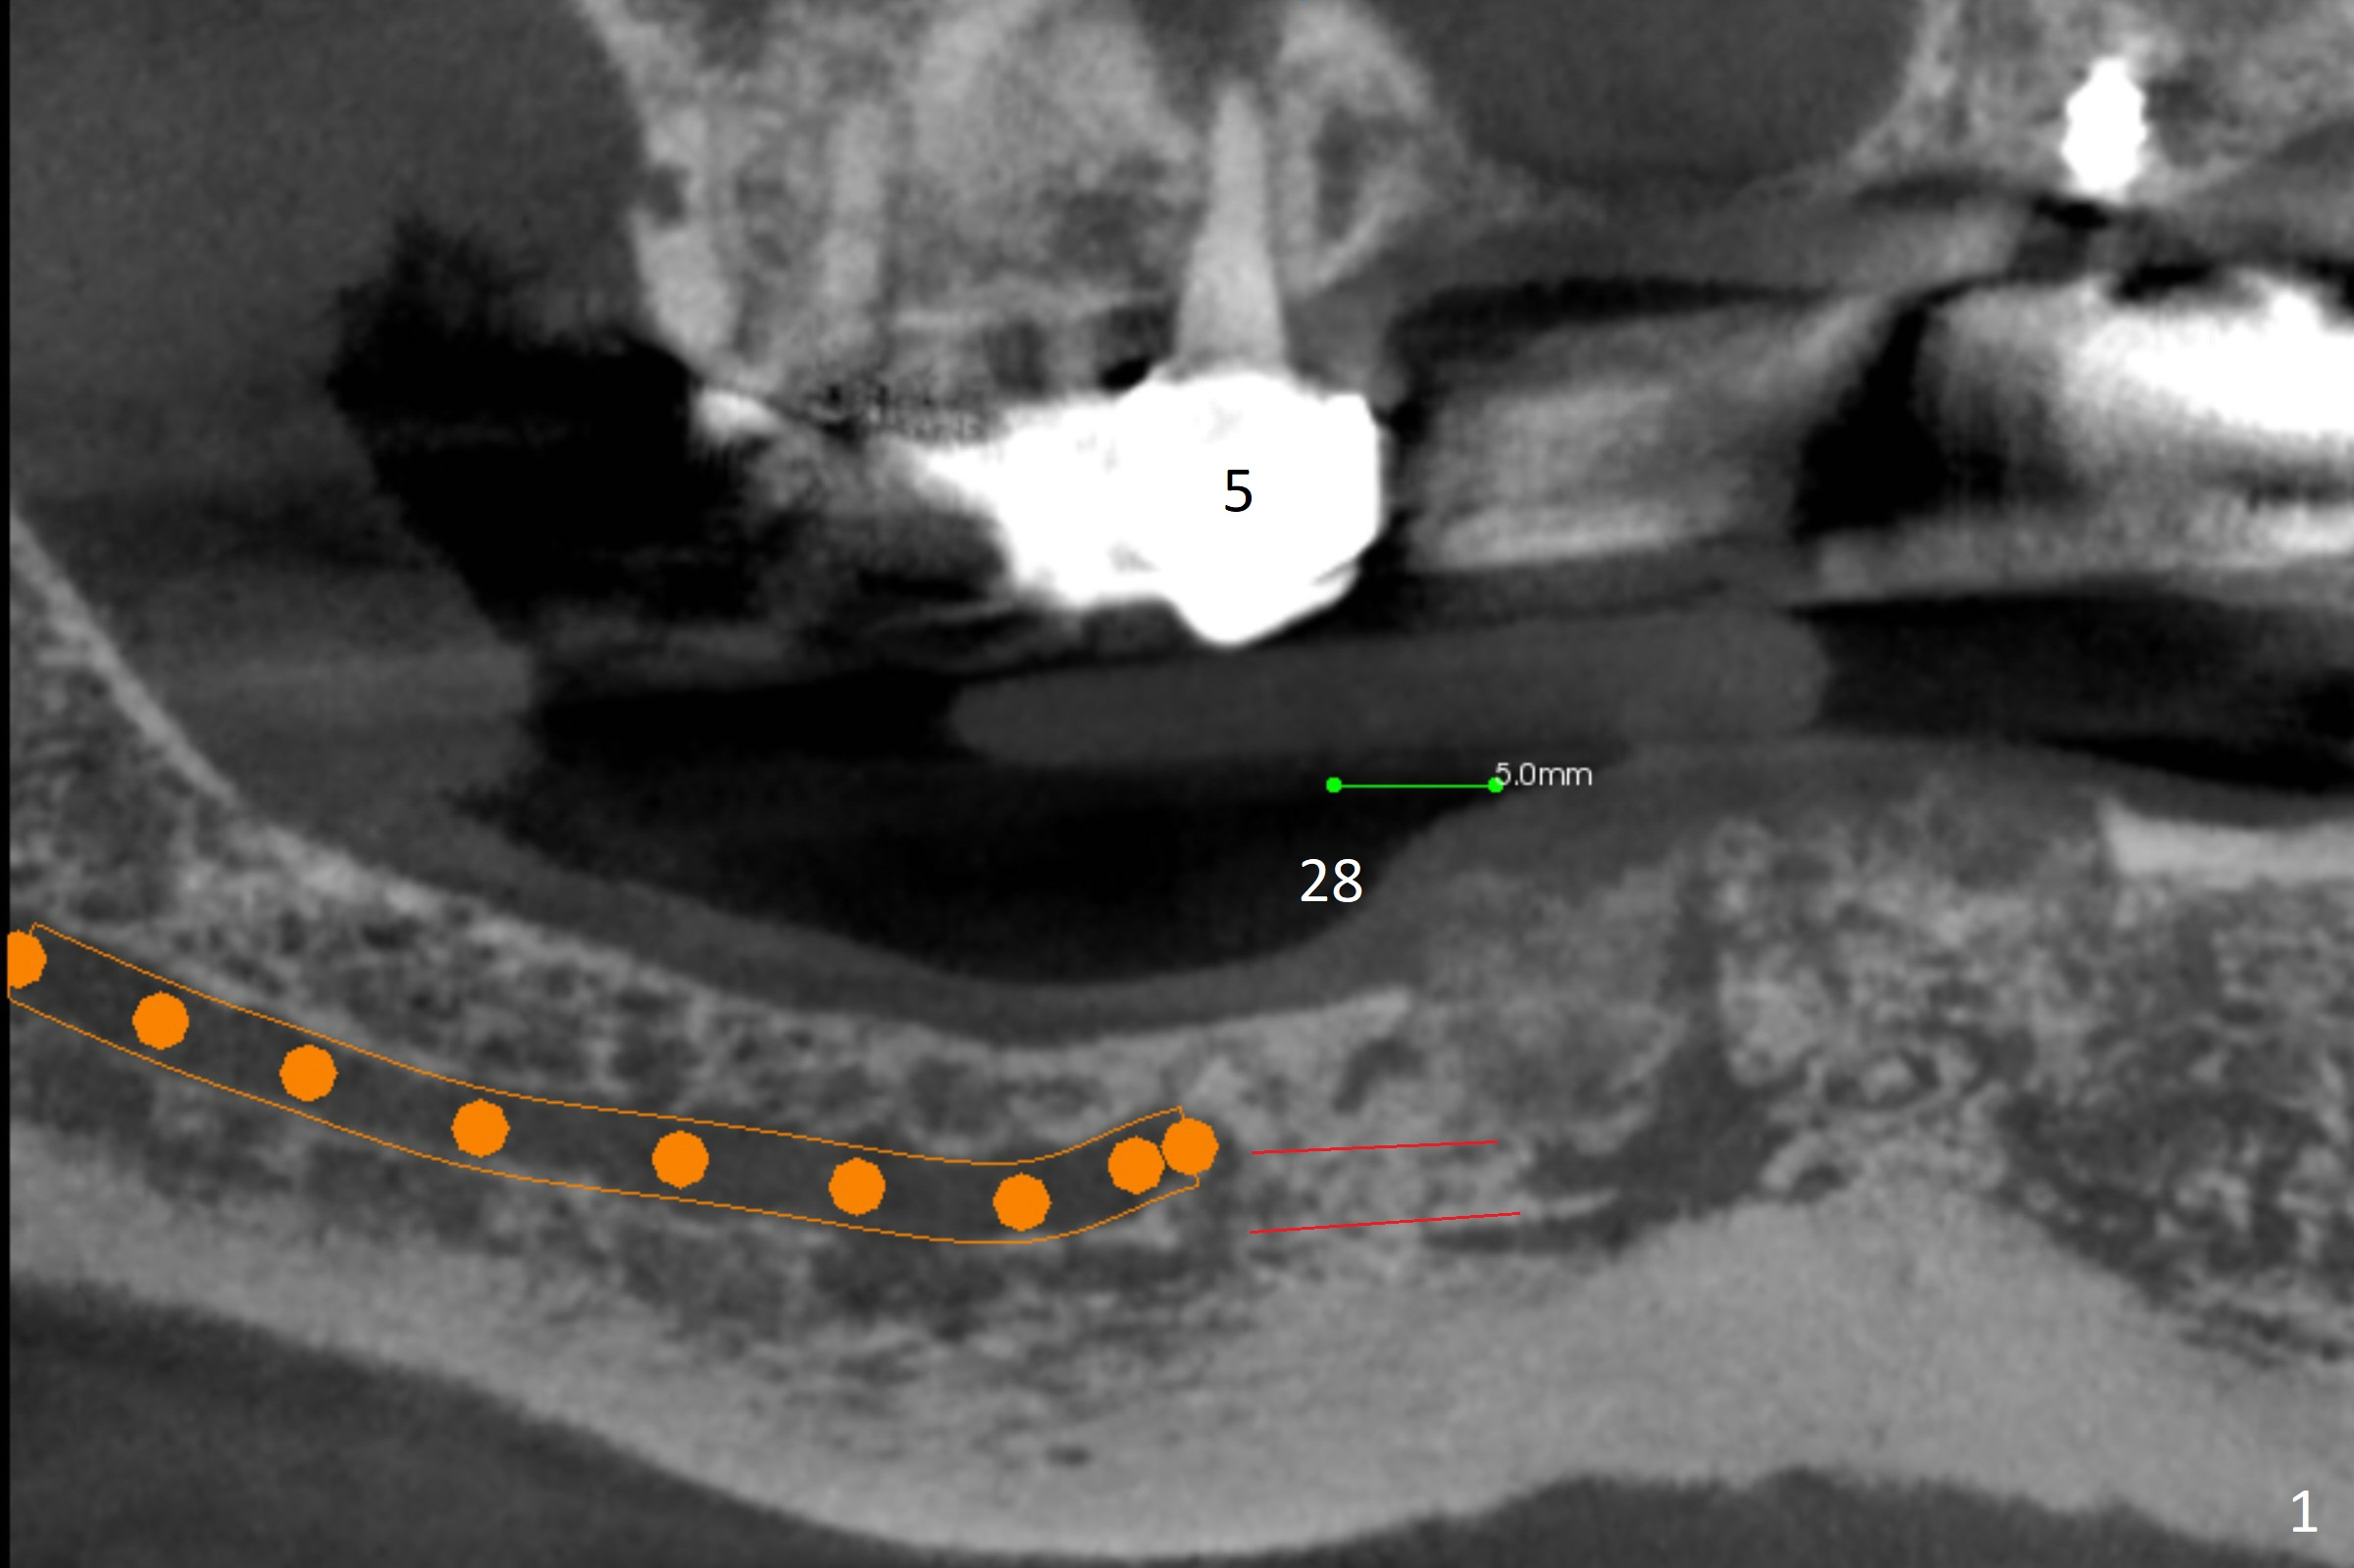

A 62-year-old woman has failed implant at #27 for the 2nd time. The crowns at #20 and 21 are loose and non-salvageable (Fig.4-6). Three implants will be placed at #20, 21 and 28 (Fig.1), since the bone height in the lower right posterior region is limited. Ball abutments will be used to retain the lower RPD. When a narrow implant is placed at #28, it will invade the Incisive Canal (Fig.2 red circle), which does not cause neuropathy, but hemorrhage. In contrast, it is safer to place a 2 mm 1-piece implant with ball type after ridge reduction (Fig.3 black triangle).